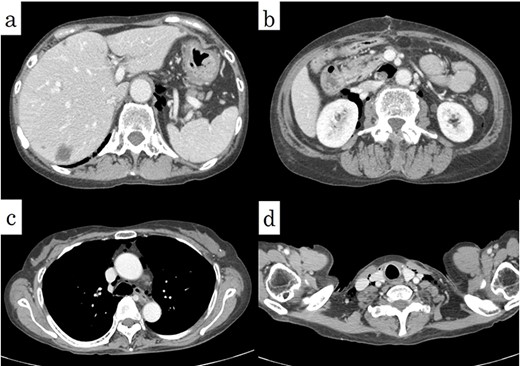

When the abdominal midline incision was performed, extensive emphysema was observed throughout the mesentery (Fig. 3a). There was no stool-like ascites in the abdominal cavity, and a small amount of cloudy ascites was observed in the pelvis. When the serosa of the sigmoid colon, where emphysema was most prominent, was incised and observed, a perforated part was found on the mesentery side of the sigmoid colon, from which stool leakage was confirmed (Fig. 3b). The diagnosis of perforation of the sigmoid diverticulum into the mesentery was made, and a Hartmann’s procedure was performed. The histopathological diagnosis was consistent with diverticulum perforation (Fig. 4).

Intraoperative findings revealed (a) pneumatosis changes in the mesenterium (arrows) and (b) perforation of the sigmoid colon at the side of the intramesenteric space (arrows).